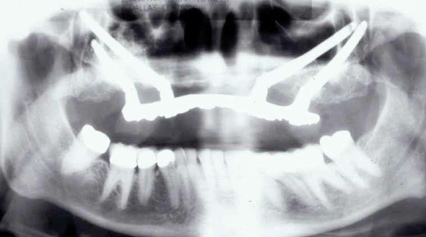

The Toronto Conference in 1982, chaired by Professor George Zarb and presented by Professor Per-Ingvar Brånemark, was a seminal event that changed edentulous treatment planning concepts irrevocably. No longer was it necessary to rebuild lost bone through grafting alone in either arch. The severely atrophic mandible, for example, could be treated with as few as four implants used to support a bone-sparing prosthesis through integrated tooth analogs, as demonstrated in Figure 1 through Figure 3. Here, an 81-year-old patient presented with severe mandibular atrophy (Figure 1) from denture wear since a very young age and had a history of being unable to manage a mandibular prosthesis despite numerous attempts at new denture construction. Four vertical machined-surface osseointegrated implants were placed in 1983 by Professor Brånemark, and all four penetrated the inferior cortex up to 3 mm to 4 mm in depth, as shown on the immediate postoperative panoramic film (Figure 2). At 4 years and 5 months, reparative bone had formed to the apices of all implants (Figure 3), and all of them remained in uncompromised function until the patient passed away at age 90.

Fig 1. 81-year-old patient had severe mandibular atrophy from many years of denture wear and had a history of inability to manage a mandibular prosthesis.

Figure 1

Fig 2. Four vertical machined-surface osseointegrated implants placed in 1983 penetrated the inferior cortex up to 3 mm to 4 mm in depth, immediate postoperative.

Figure 2